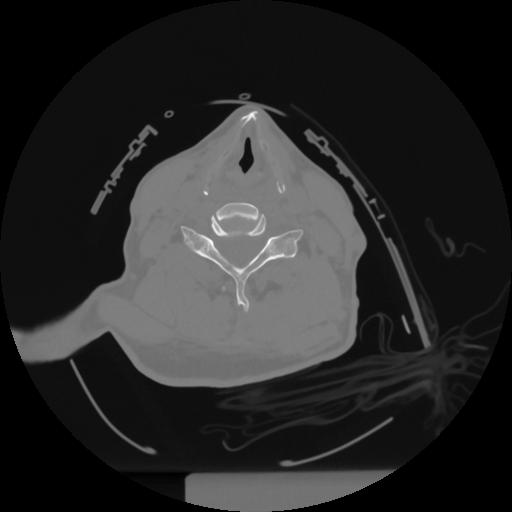

12 P.BLANDAS,,Vol,0.5,P.BLANDAS,,